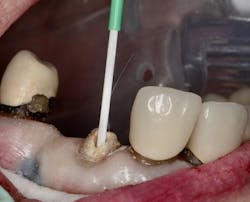

Figure 1: Occlusal image of finished root canal prep after gutta-percha removal

The root canal on No. 10 was completed using the WaveOne Gold system (Dentsply Sirona). Upon completed obturation, care was taken to remove only excess gutta percha from the canal using a warmed endodontic plugger. Removal extended approximately 4 mm to 5 mm into the canal space (figure 1).